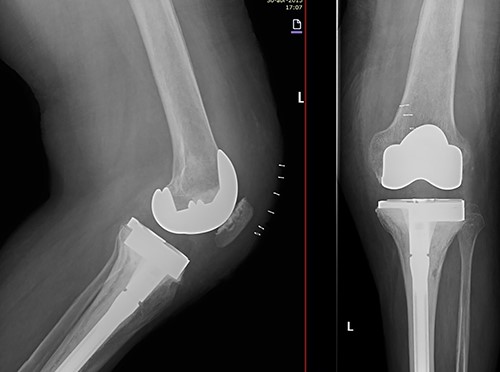

In the early postoperative period, no complications were detected, with pain decrease. After 4 years, the patient’s active ROM was 0–110° bilaterally, with no signs of radiological loosening (Fig. 9) and no pain, leading an unrestricted walking daily life without aids.

Both knees standing radiographs at 4-year follow-up with no signs of radiological loosening.